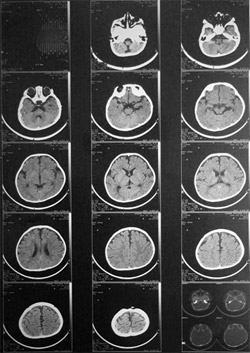

影像学检查

• 主要通过颅内CT或磁共振成像检查有无颅内出血等异常。

• 头颅CT可显示枕叶皮质软化灶。